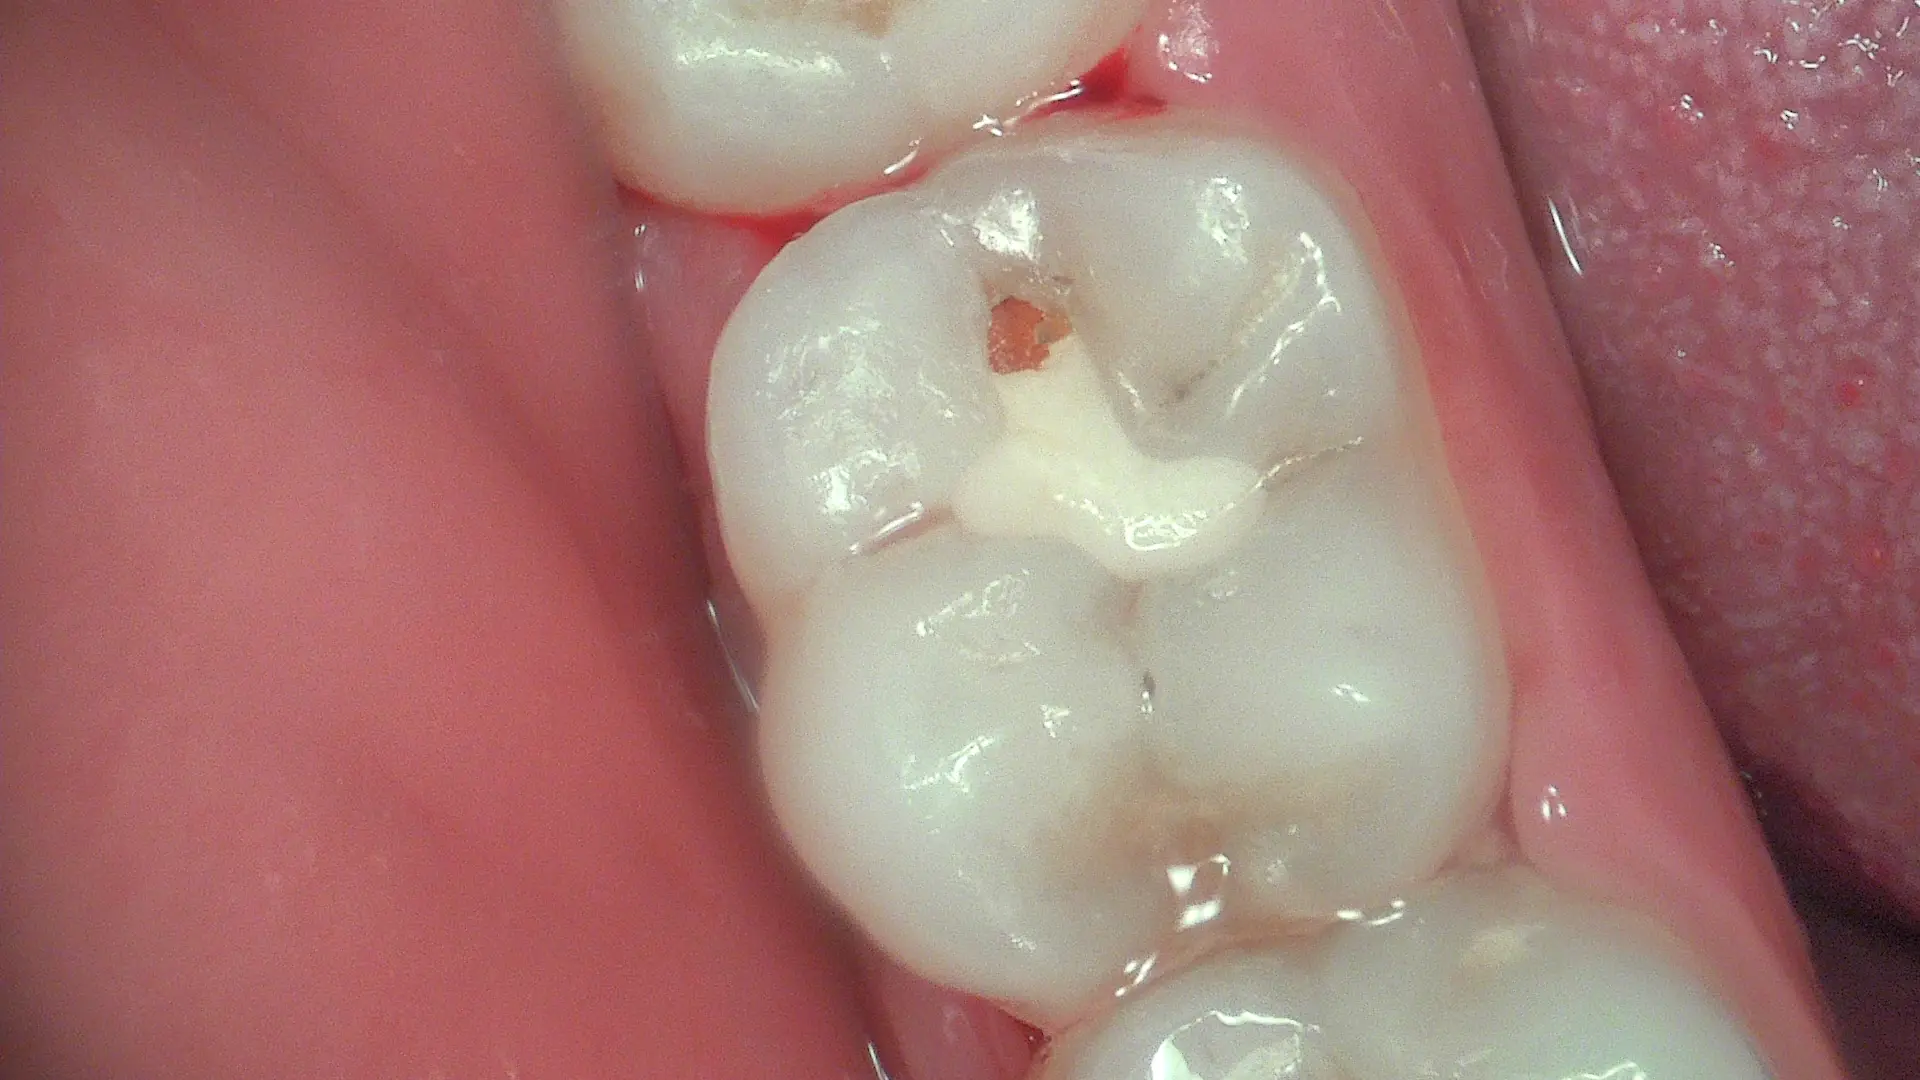

True-Colour Clinical Photography

Full HD white-light mode for standard clinical images — restorations, fractures, gingival condition and patient communication. Sharp, true colour at 1920×1080.

Experience the exceptional Full HD detail and fluorescence diagnostics in real patient cases — from early caries detection to minimally invasive restorations.